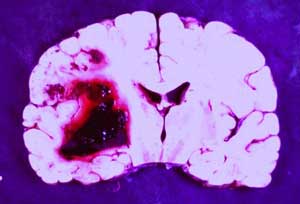

Sigaranın neden olduğu en önemli hastalık grubu kanserlerdir. Sigara, akciğer kanseri başta olmak üzere soluk borusu, gırtlak, ağız, dil, dudak,

yemek borusu, mide, pankreas, mesane, böbrek ve kadınlarda rahim ağzı kanserlerine neden olmaktadır. Tüm kanser ölümlerinin % 30 unun,

akciğer kanserinden ölümlerin ise % 90 ının nedeni sigaradır. Günde 1 paket sigara içen birinde akciğer kanserine yakalanma riski hiç içmeyen

birine oranla 20 kat fazladır.

İçtiğiniz her sigara sizi kansere bir adım daha yaklaştırmaktadır !